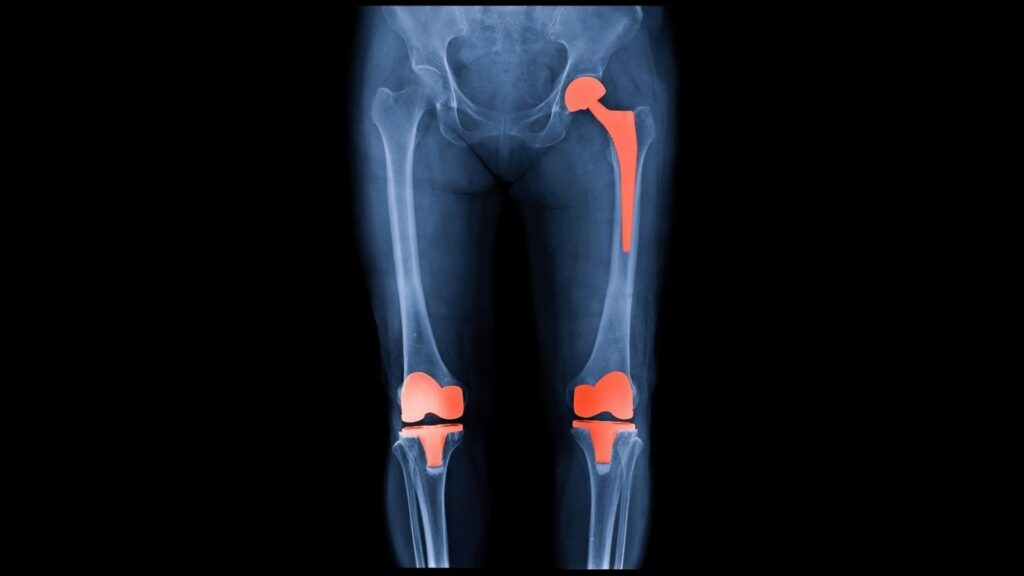

Protez Çeşitler

Diz protezi

- Total diz protezi: Eklem yüzeyleri ileri derecede bozulmuş hastalarda

- Parsiyel (yarım) diz protezi: Uygun hastada daha sınırlı eklem hasarında seçenek olabilir (hasta seçimi kritiktir)

Kalça protezi

- Total kalça protezi: Kalça kireçlenmesinde ağrıyı azaltmak ve hareketi artırmak için en etkili cerrahi seçeneklerdendir.

Beklenen fayda: Ağrının azalması ve yürüme kapasitesinin artmasıdır. Büyük ortopedik merkezlerin hasta bilgilendirmelerinde, diz protezi sonrası hastaların önemli bir kısmının sonuçları “iyi/çok iyi” olarak değerlendirdiği belirtilir.